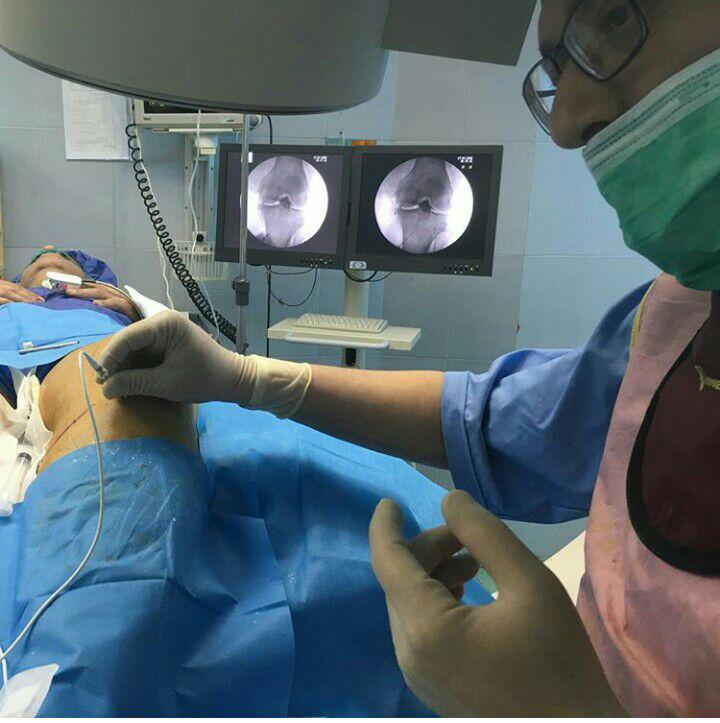

-لیزر(جراحی بسته) دیسک کمری

استفاده از روشهایی مانند تزریقات تخصصی (مانند اپیدورال، بلوک عصبی)، طب سوزنی، فیزیوتراپی، تحریک الکتریکی عصب و روشهای کم تهاجمی جراحی.